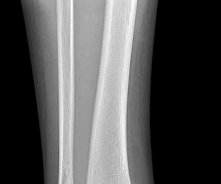

Question 37

An 18-month-old male is evaluated for congenital pseudarthrosis of the tibia (CPT). Examination reveals anterolateral bowing of the affected leg. Which genetic condition is most strongly associated with this finding?

A newborn infant is noted to have severe anterolateral bowing of the right tibia. There are no fractures present on initial radiographs. The infant is at highest risk for developing congenital pseudarthrosis of the tibia (CPT). Which of the following genetic conditions is most strongly associated with this finding?